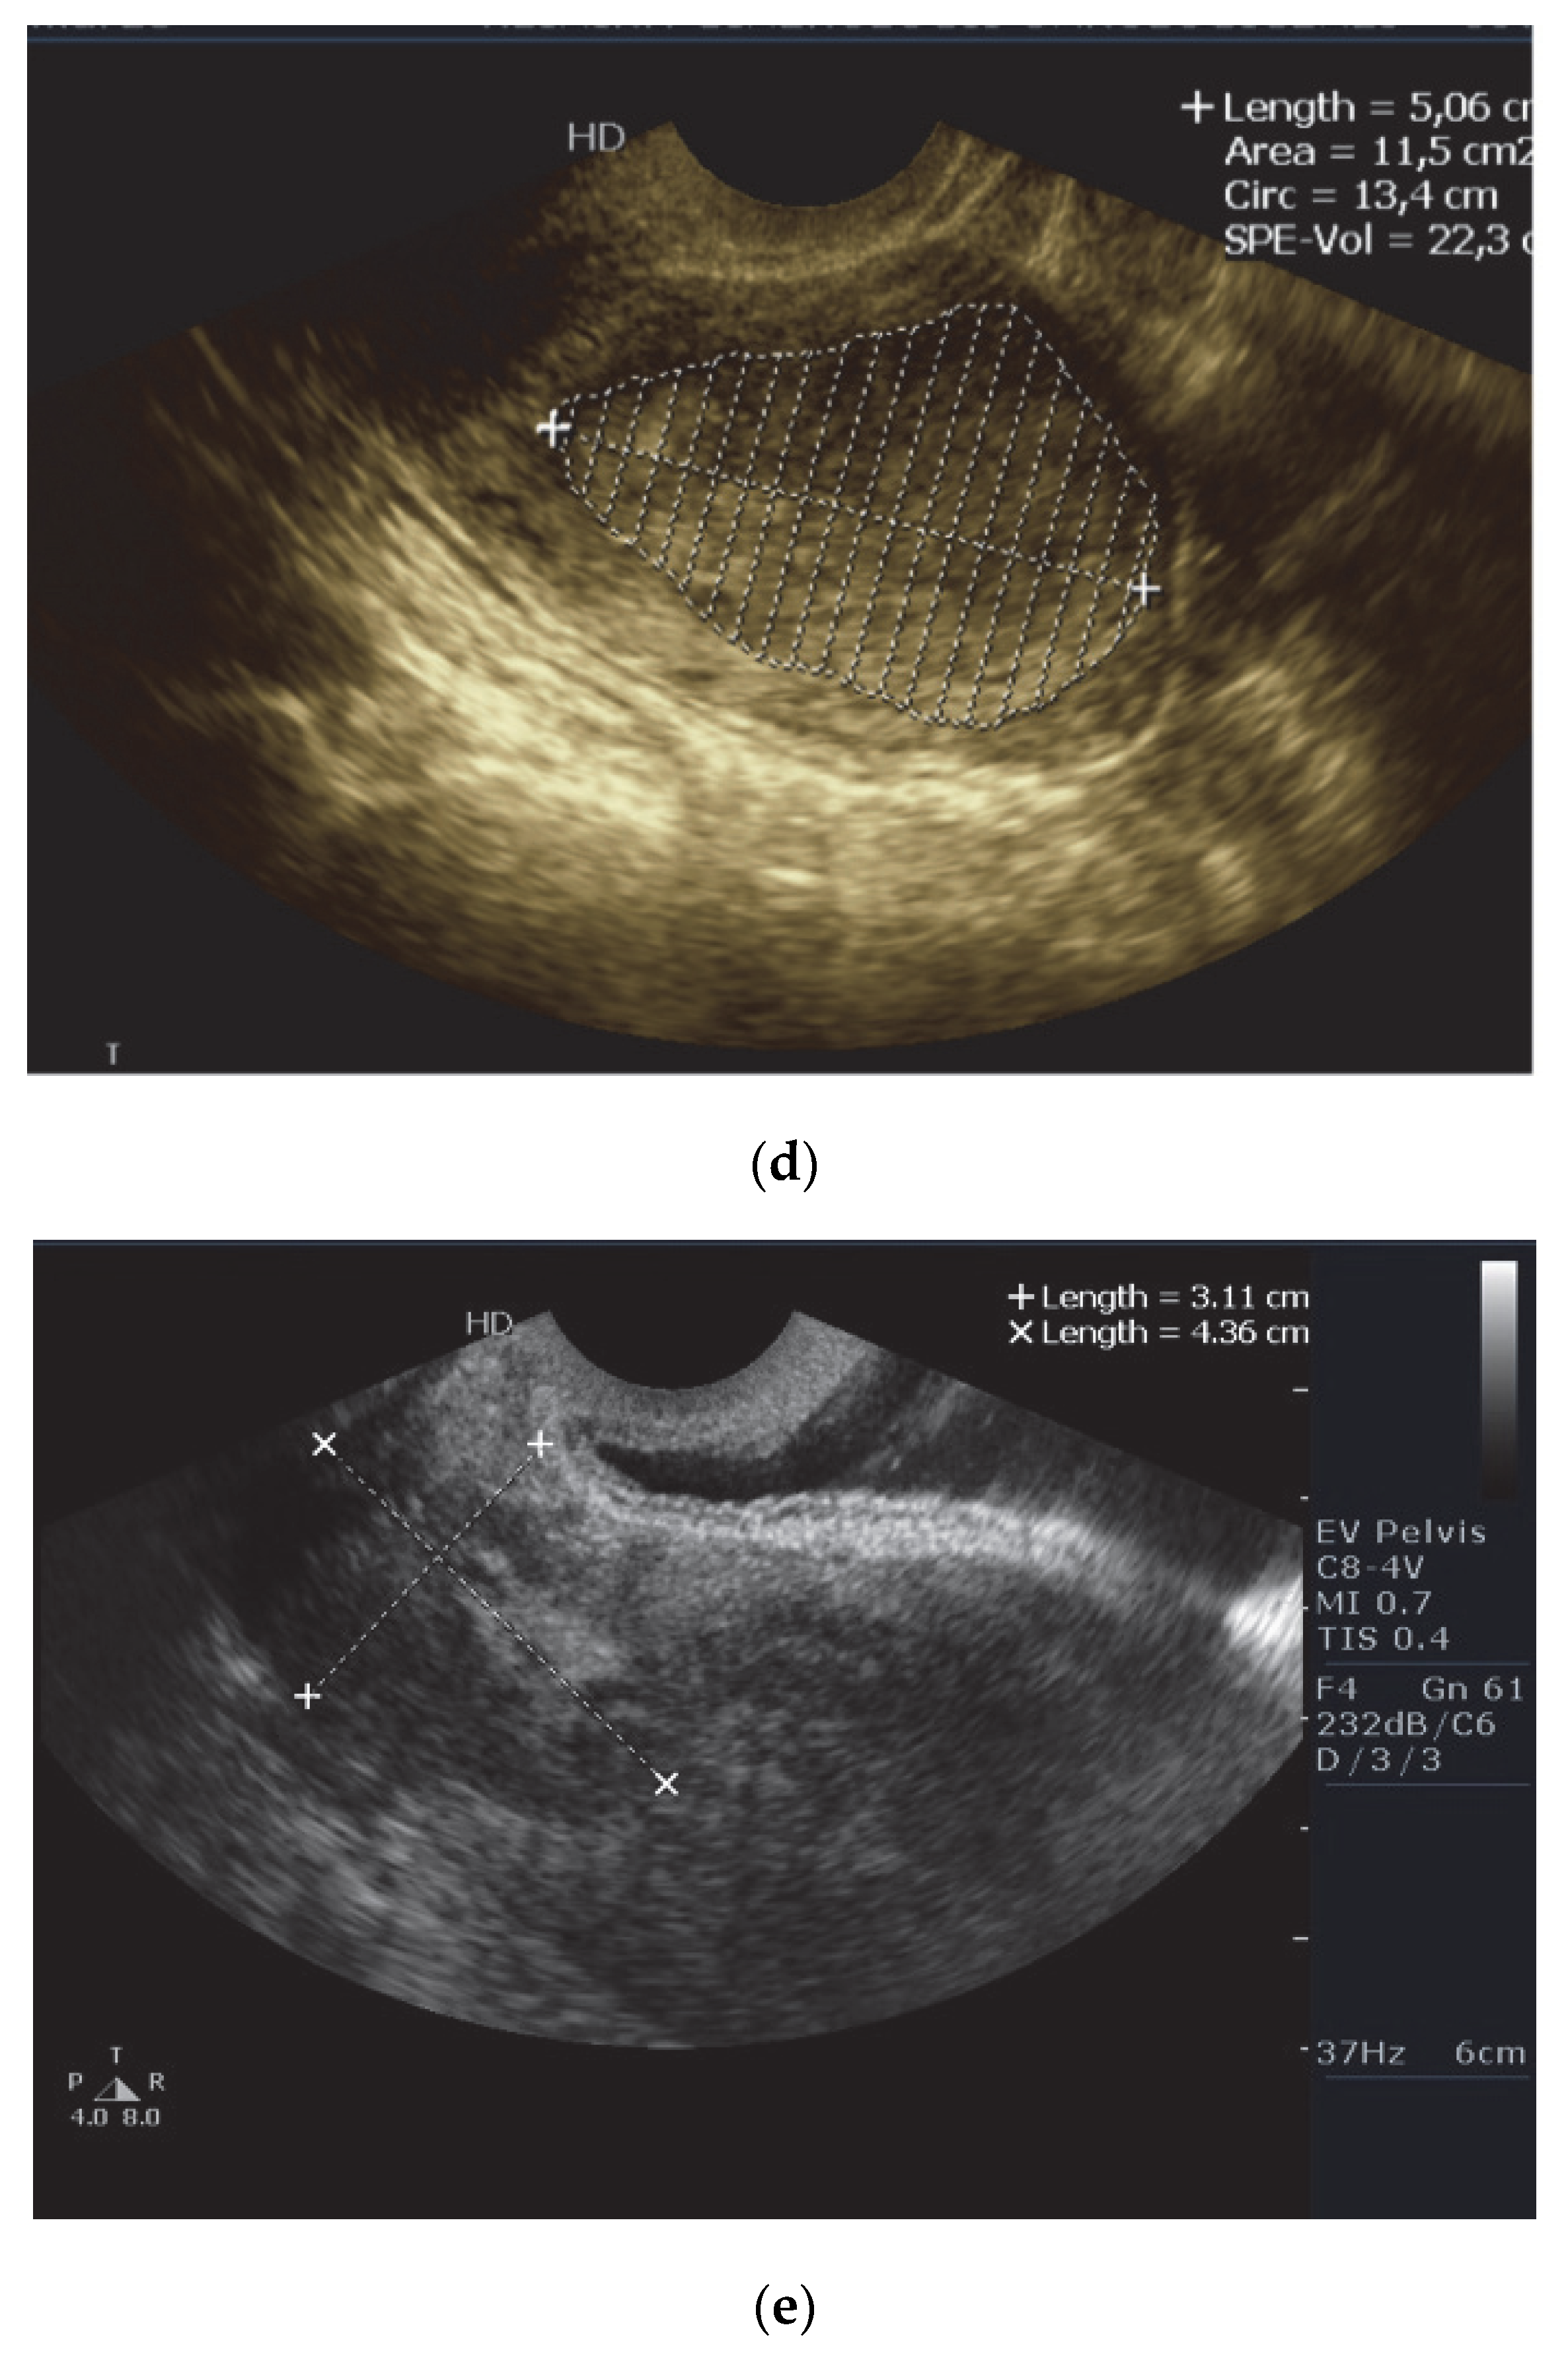

2.2. Ultrasound Examination